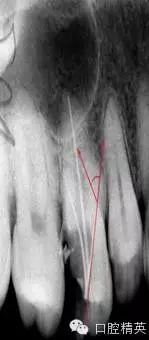

在根管治療的幾年經(jīng)驗(yàn)中,有些感悟愿與朋友們分享,不到的地方請(qǐng)同仁指正。在做好根管治療時(shí)我們首先要攝片分析根管難度選擇合適器具合適方法進(jìn)行治療,根管難度評(píng)估:簡(jiǎn)單根管(5-10度)

,中等難度根管,(10-25度)復(fù)雜難度根管(大于25度)

2中等難度根管